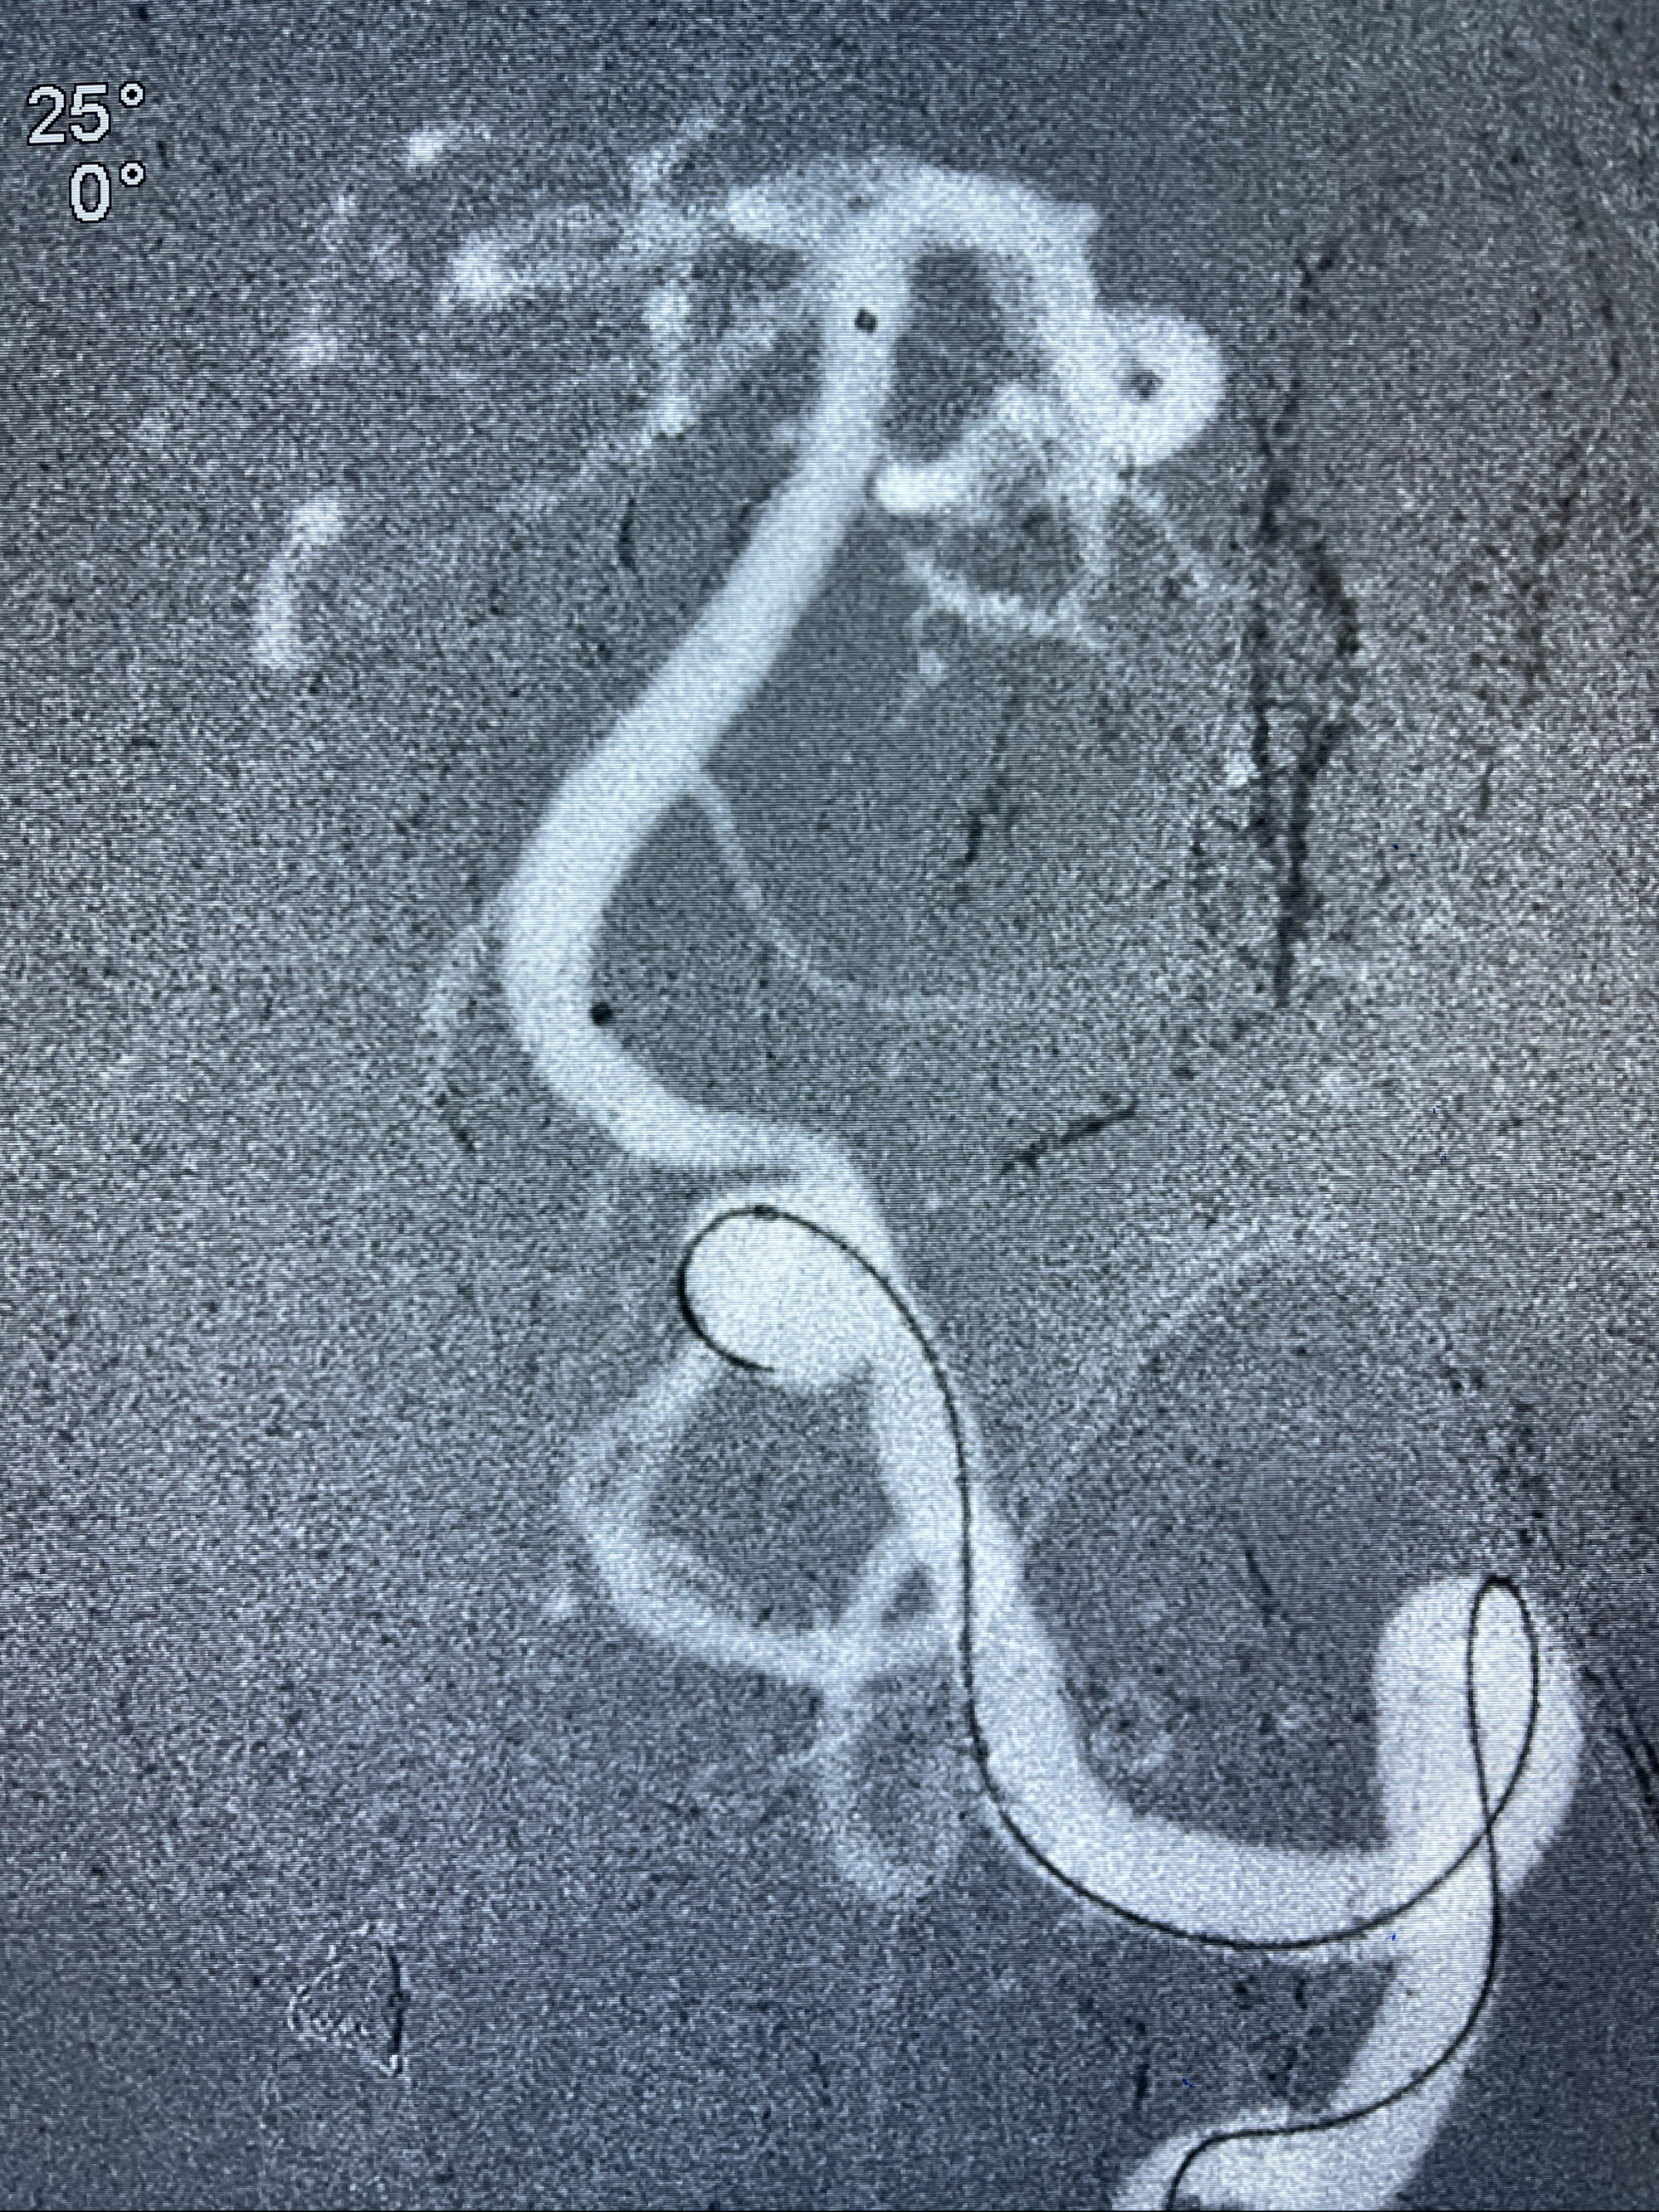

左侧椎动脉V4夹层动脉瘤多支架辅助栓塞:

1.Enterprise4.0-23mm;

2.Tubridge3.5-30mm密网支架

支架到位

支架释放,透视下